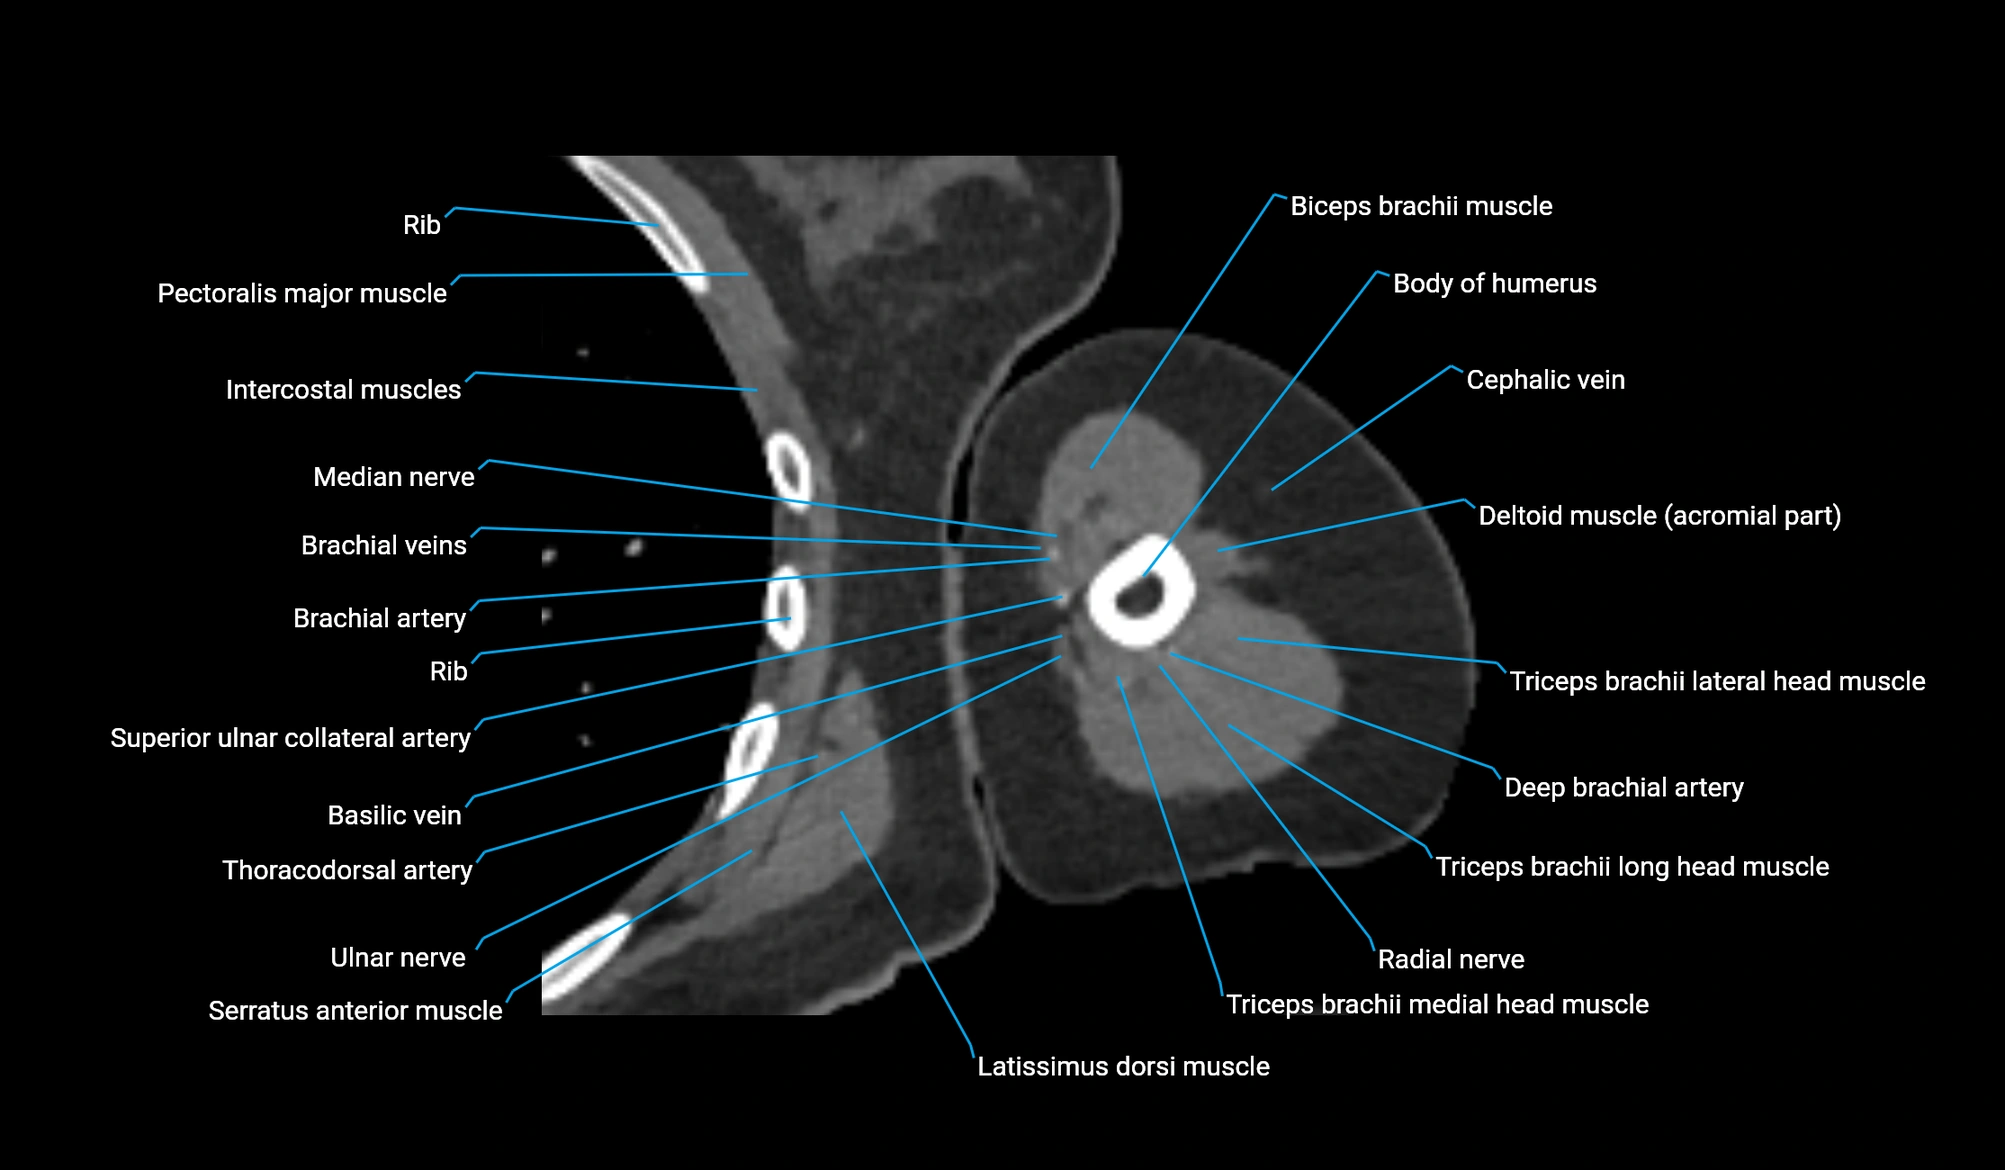

- Basilic vein

- Biceps brachii muscle

- Body of humerus

- Brachial artery

- Cephalic vein

- Clavicular part of deltoid muscle

- Deep brachial artery

- Lateral head of triceps brachii muscle

- Long head of triceps brachii muscle

- Medial head of triceps brachii muscle

- Median nerve

- Radial nerve

- Superior ulnar collateral artery

- Teres major muscle

- Thoracodorsal artery

- Triceps brachii muscle

- Ulnar nerve